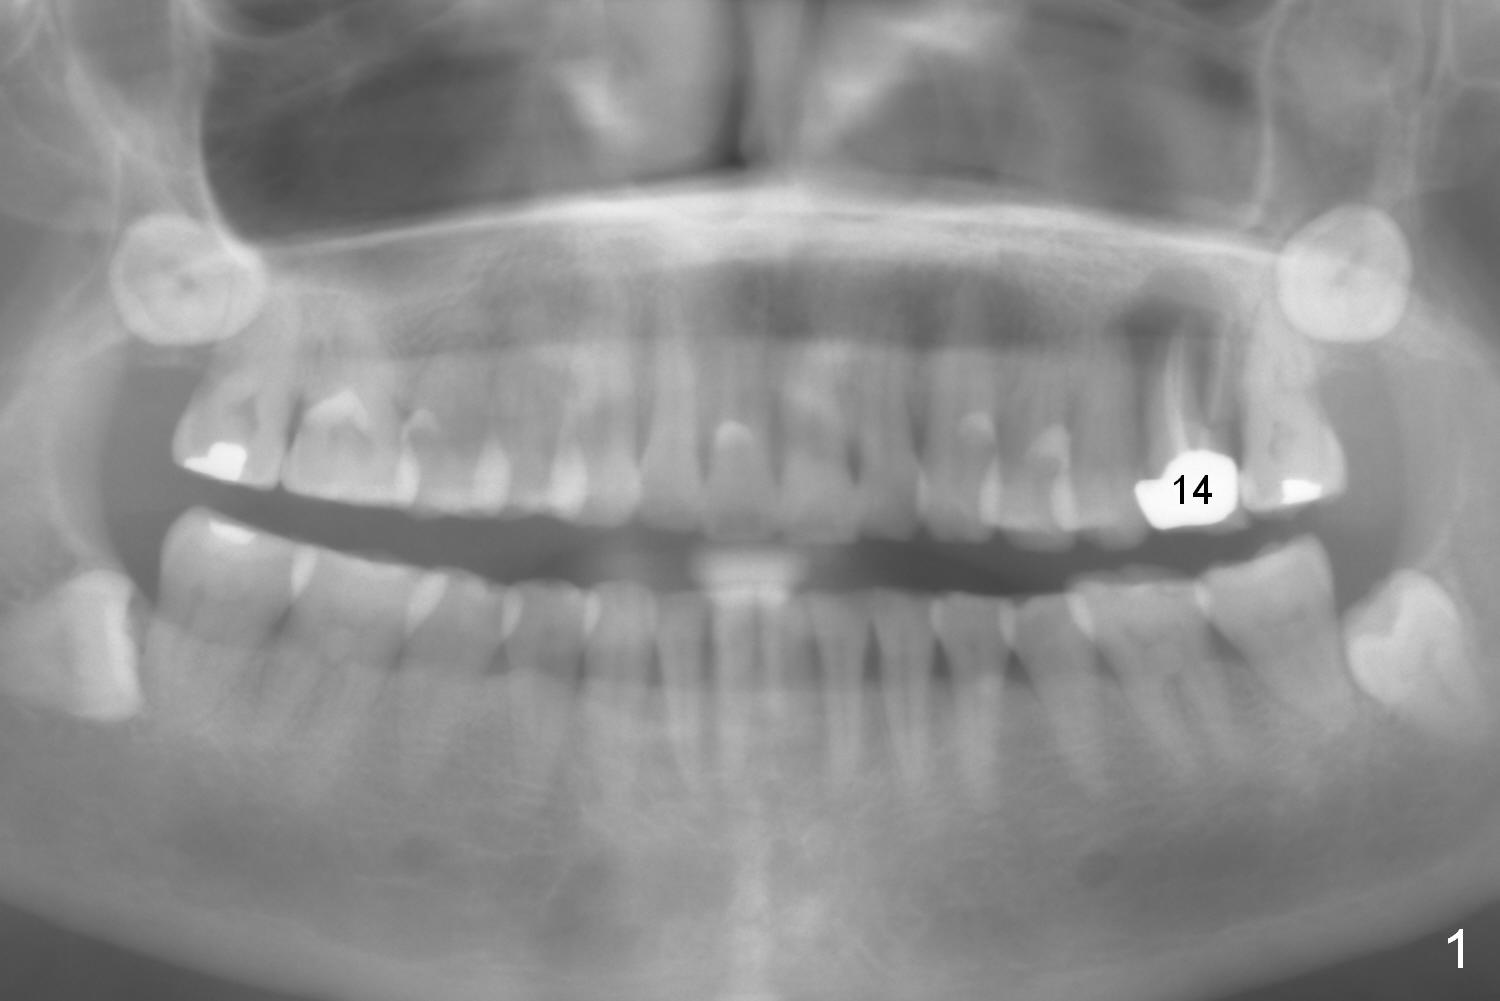

A 54-year-old woman has nocturnal pain at the tooth #2 (Fig.2), one year after extraction of the tooth #14 (Fig.1). A mesiodistal crack line is found at root canal therapy (Fig.3 arrowheads). The tooth appears to be nonsalvageable. The socket is either single or 3. Cut and soak 3 large pieces of gauze in Metronidazole. When the tooth is extracted, we will decide whether the gauze needs to be cut further. Depending upon the size of the septum, a relatively small (4.5x9 mm Fig.4) or large (6.5 mm) implant will be placed. The largest pair abutment will be installed to close the socket.